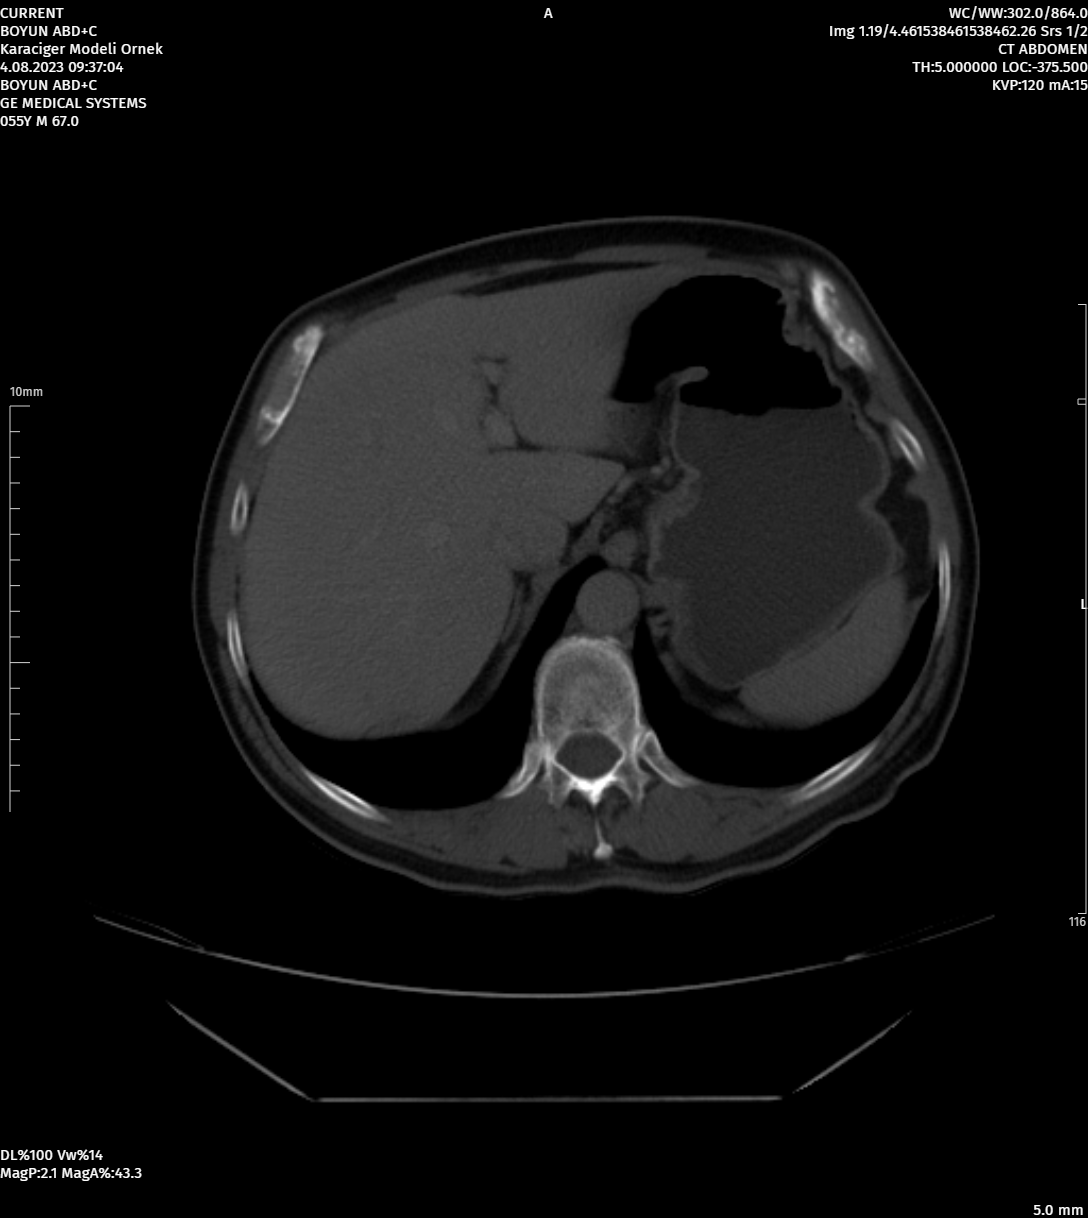

MoreAdvanced Image Processing Tools

Image Processing Tools That Can Work with Different Segmentations